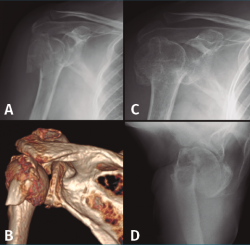

Hay muchas clasificaciones para la fracturas de húmero proximal, las más conocidas son probablemente la clasificación de Neer(2) publicada en 1970 y la clasificación AO(6), que divide las fracturas en 3 grandes grupos –A, B y C– y subgrupos haciendo énfasis en la irrigación vascular de la cabeza del húmero. Otra clasificación es la de Hertel, también conocida como LEGO, más didáctica y que presenta 12 tipos(7). Para todas estas clasificaciones está demostrado que su reproducibilidad no es muy alta y depende mucho de la experiencia del cirujano(8). De cara a la definición de fracturas complejas en este artículo, consideramos que son, según la clasificación de Neer, las de 3 o 4 partes, las fracturas 3 o 4 partes con luxación y las fracturas head-split(2) (Figura 1).

En el grupo que estamos analizando de pacientes en edad laboral con fractura compleja de húmero proximal su aplicación es limitada. Solamente quedaría indicado probablemente en pacientes mujeres mayores de 60 años con fracturas de 3 o 4 partes no muy desplazadas, con mala calidad ósea, un trabajo sin grandes requerimientos físicos y una vida extralaboral no muy activa (Figura 2). En estos pacientes la inmovilización con un cabestrillo de 4-6 semanas y la posterior rehabilitación funcional constituyen el tratamiento habitual.

Figura 2. Evolución radiológica del tratamiento conservador de una fractura de húmero proximal derecho. A: radiología simple anteroposterior; B: reconstrucción de la tomografía computarizada de la fractura de 4 partes desplazada; C y D: evolución radiológica del tratamiento conservador.